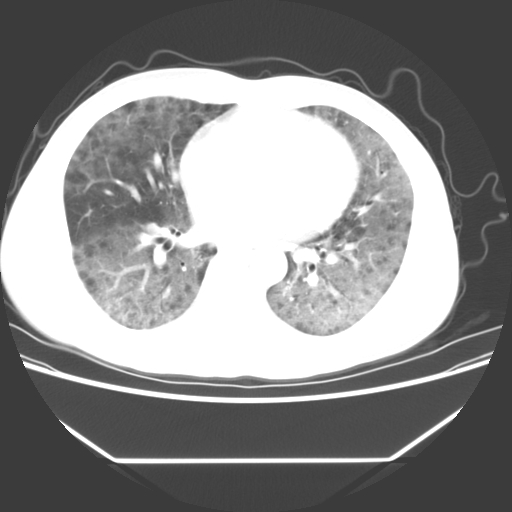

病人55岁,咳嗽,胸闷

忘了传病史了,病人55岁,咳嗽,胸闷

两肺部呈“毛玻璃”状改变,原因待查考虑感染性病变

病人是否发烧,两肺“磨玻璃”影,其间见空气支气管征和碎路石征。考虑肺泡蛋白沉着症。

两肺广泛对称磨玻璃样影,密度不均,考虑机遇性肺部感染。

双肺弥漫磨玻璃样病变,病史很重要。有感冒或发烧史,甲流不除外。无发烧可考虑肺泡蛋白沉积,但肺泡蛋白沉积边缘往往较清晰,与正常肺组织分界清晰

两肺弥漫间质性病变,考虑肺泡蛋白沉着症。建议进一步检查。